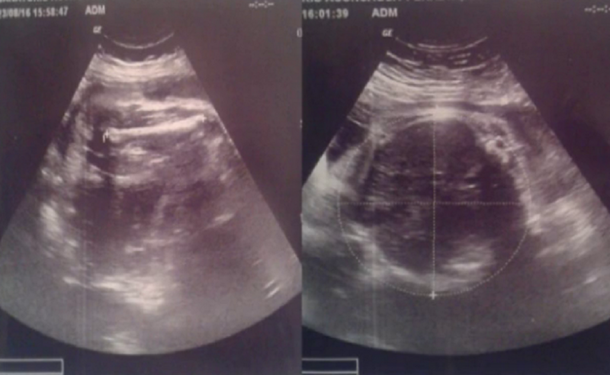

Una joven de 15 años aseguró que fue madre de mellizos, pero que tras el parto en una clínica privada de Córdoba sólo le dieron uno de los bebés que figuraba en la ecografía que se había realizado un mes antes.

La madre asegura que en la ecografía se veían a dos bebés. Foto: canal 10.

Sol Peralta quien junto a su familia protestó en las puertas del Sanatorio Privado Aconcagua, denunció que la clínica le entregó el pasado 23 de agosto (en su semana número 37 de embarazo) una ecografía que mostraba cómo avanzaba la gestación de mellizos en su vientre.

Sin embargo, el día del alumbramiento, el 19 de septiembre, el centro de salud sólo le entregó a Lucas, un varón, pero nunca a Martina, la niña.

La madre de la joven, María Sandra Tula, quien la acompañó de cerca hasta la puerta del quirófano, ratificó en Radio Universidad lo que contó de su hija a Canal 10 y aseguró que la ecografía fue realizada en el mismo sanatorio donde se desarrolló la intervención.